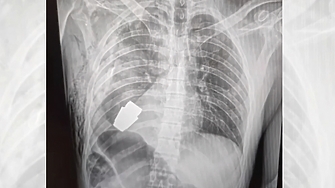

Военни лекари извършиха успешно операция по изваждане на невзривена граната

...... Верба без електрокоагулация, тъй като гранатата можела да детонира всеки момент.Отбелязва се, че след операцията раненият войник е изпратен за по-нататъшно лечение и възстановяване.Снимка: БГНЕС

Военни лекари в са извадили граната ВОГ от гърдите на

...... състоянието му е стабилно“, съобщава и Антон Геращенко, съветник към вътрешното министерство на Украйна. Говорителят на в страната уточнява, че войникът е на 28 години.

...... роден през 1994 г., сега е изпратен за рехабилитация, състоянието му е стабилно. Мисля, че този случай ще влезе в учебниците по медицина", казва тя.

...... гранатата може да се взриви по всяко време", допълва зам.министърът на отбраната."Хирургичната намеса е успешна и пострадалият военнослужещ е изпратен за по-нататъшна рехабилитация", пише Маляр.